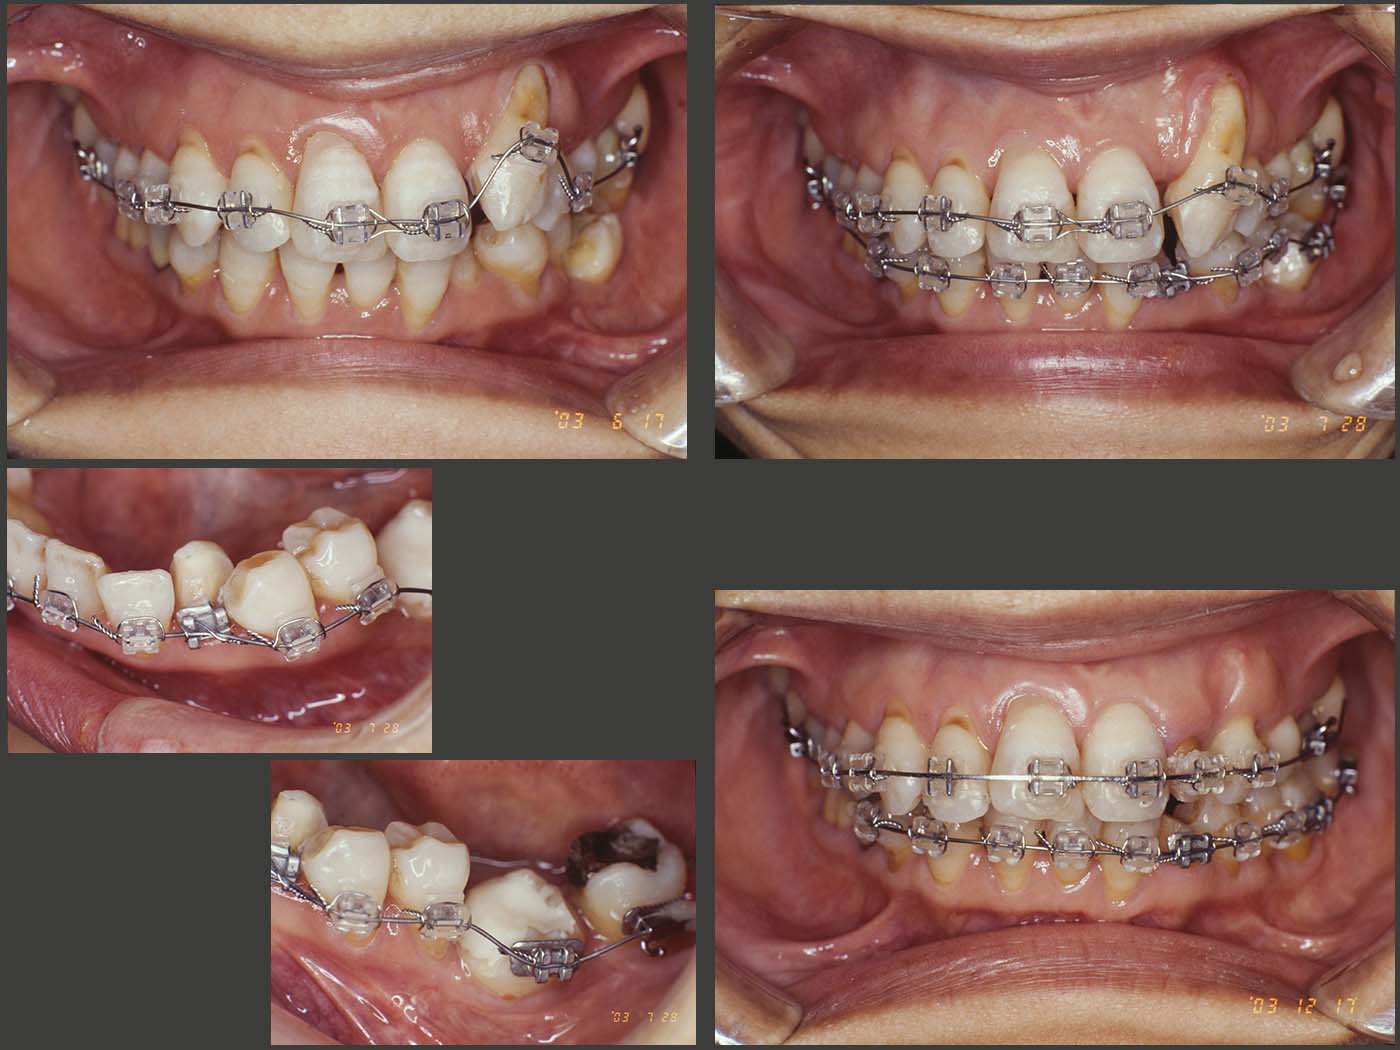

移植された左下6が安定したところで,左上2および3をどう処置するか迷った.患者さんは,頰側の歯根の露出が著しく大きい左上3の審美性の悪さを気にしていることから,残根状態の左上2でなく,有髄歯である左上3を抜去することにした.またこの際,頰側歯槽骨を増大させる目的で,2003年6月,左上3に矯正的挻出を施した.8月,最後のご奉公が終了したため,左上3を抜去した.

また12月にかけて,左上2の唇側移動,左下3,4,5の叢生の解消および頰側傾斜埋入された左下6のアップライトの目的で歯科矯正を行った.なお,左下3は歯冠幅径を小さくする必要から抜髄せざるを得なかった.